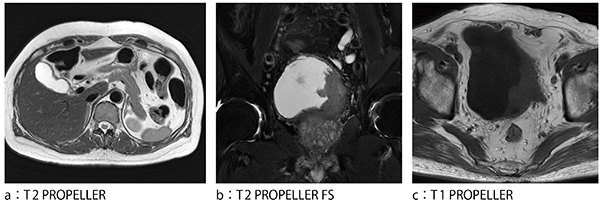

体動補正アプリケーションとして広く普及しているPROPELLER法だが,SIGNA Worksプラットフォームでは,ブレード内をマルチショットに分割可能(MB:マルチショットブレード)となり,T1強調やPD強調画像,さらにはASPIR型の脂肪抑制や横隔膜同期との併用など,より体幹部領域での活用方法が広がった(図1)。

図1 体動補正機能の全身応用

(画像ご提供:社会医療法人財団石心会 川崎幸病院様)